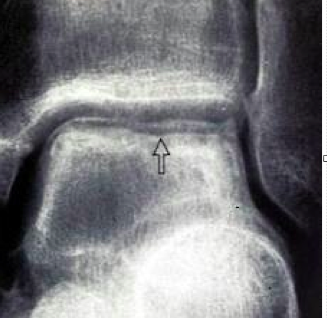

What is the sander’s classification of calcaneus fractures